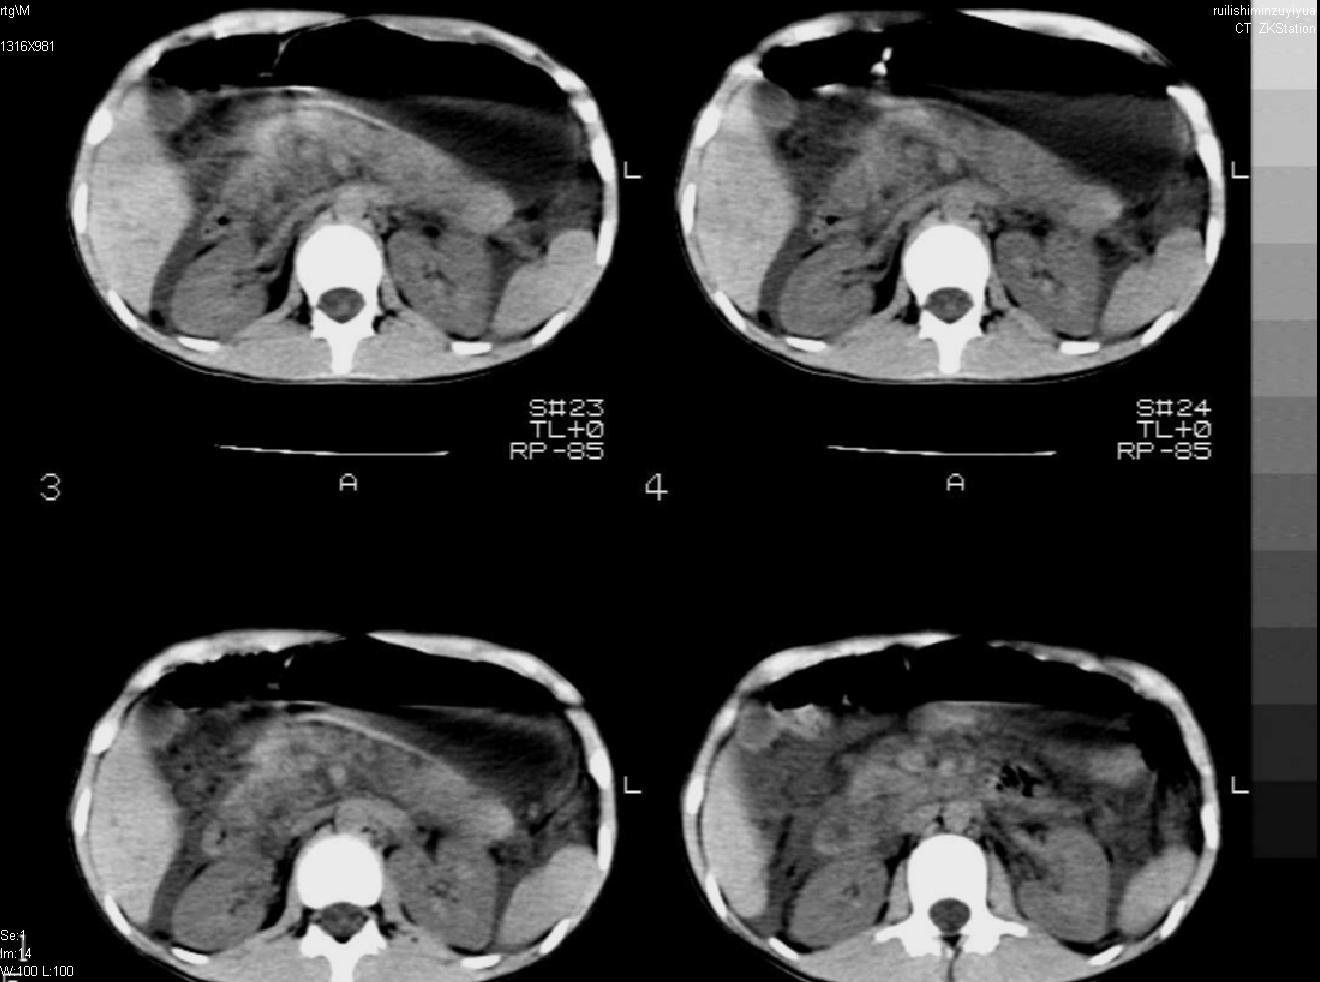

标题: PED0282:女,10岁,上腹疼痛2周 [打印本页]

标题: PED0282:女,10岁,上腹疼痛2周

b超:胆囊结石。疑坏死性胰腺炎

支持小儿急性坏死性胰腺炎。

支持急性胰腺炎。

支持急性胰腺炎并腹膜炎。

急性胰腺炎,腹腔积液